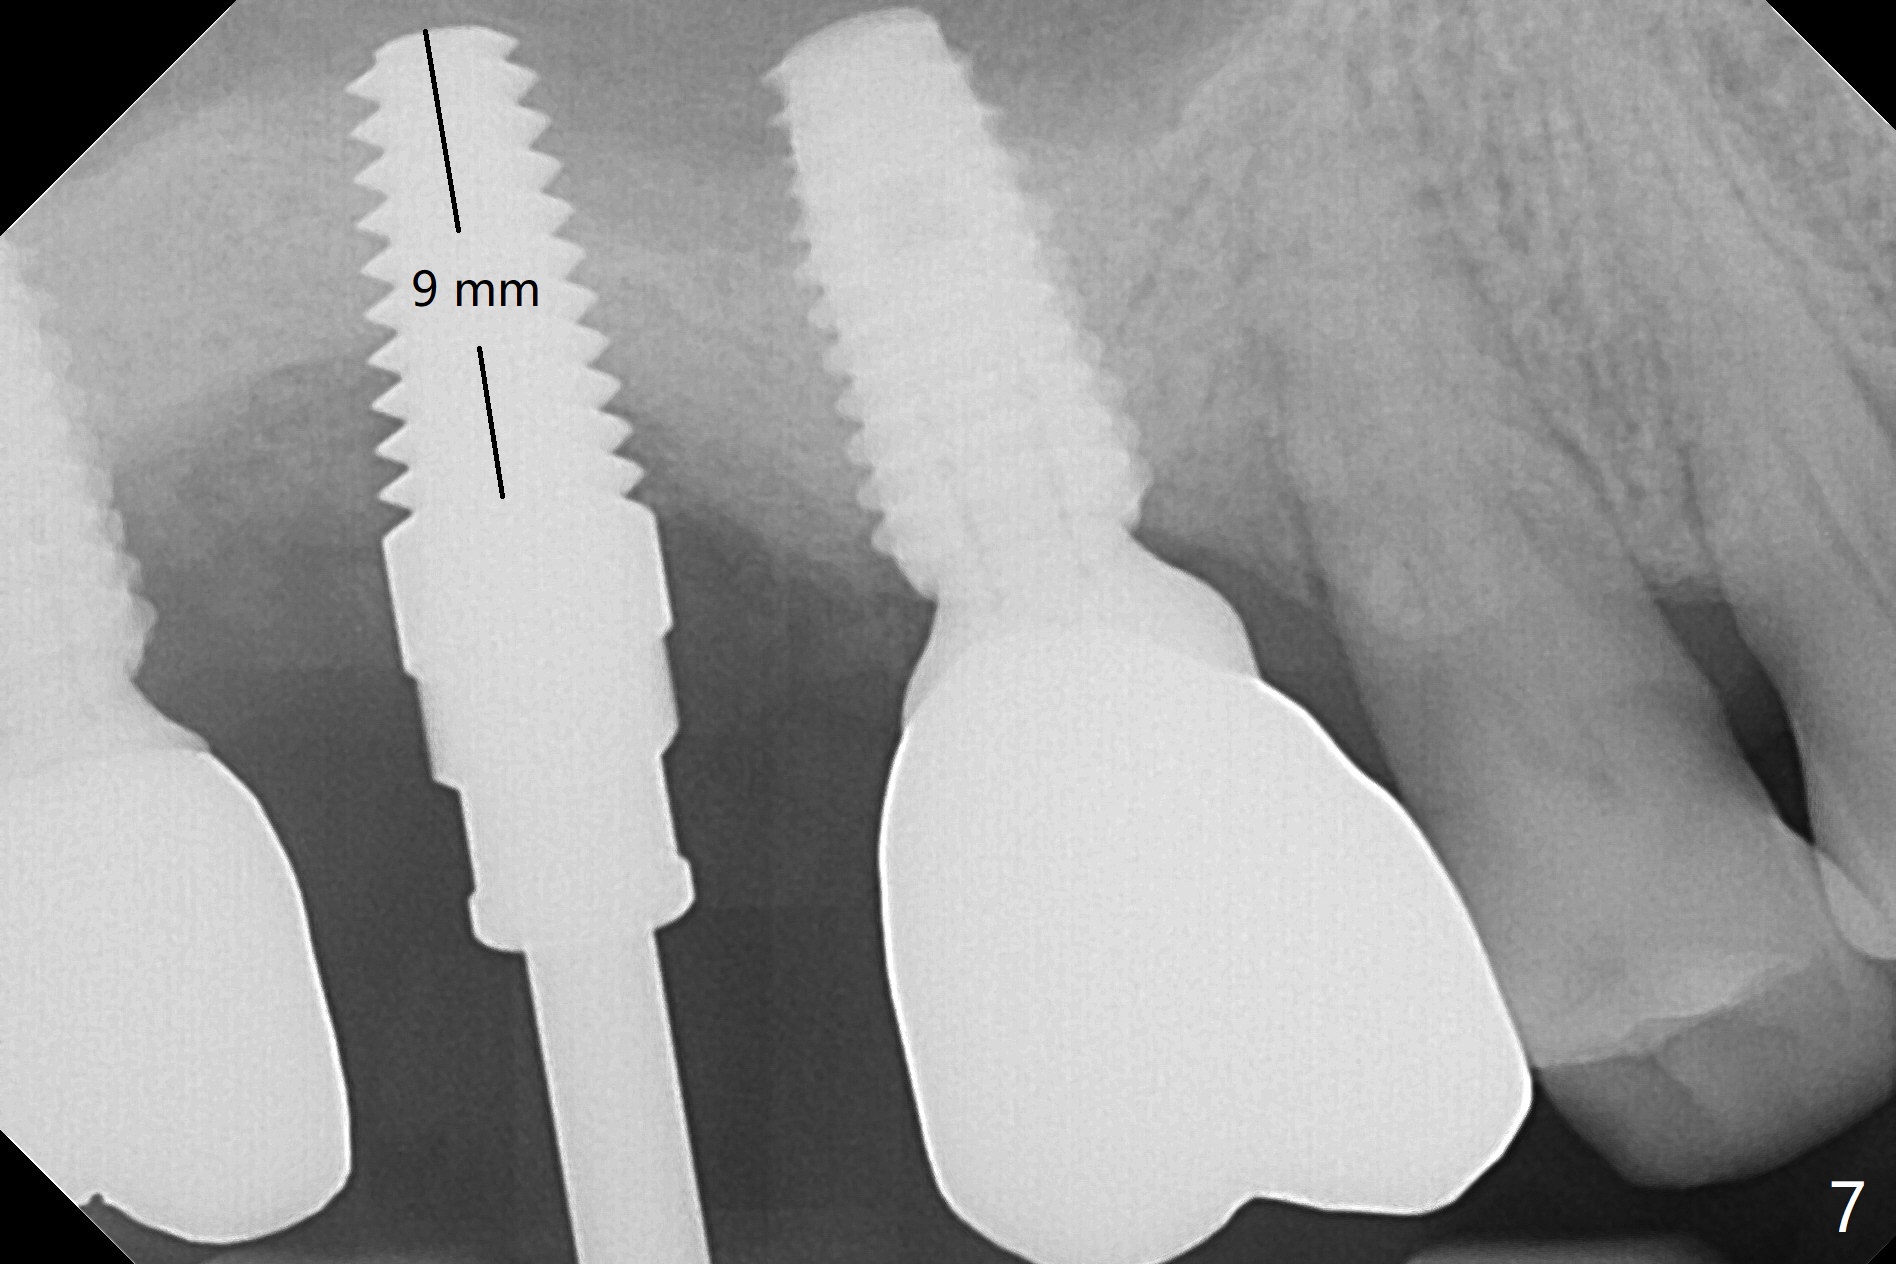

Due to time constraint (he may move out of state), implant placement will be free hand with palatal incision (Fig.5 P).  Surgical stent will be ready.  Since the patient is a heavy bruxer, a 5 or 6 x14 mm tissue-level implant will be placed using DIO Sinus Lift Master Kit and Bone Expander Kit (Fig.6).  Prepare water pump syringe.  The first 6 mm osteotomy with regular drills (1.2 and 2.0 mm) is easy and soft, whereas the last 1-2 mm is hard.  In the end, the sinus membrane is perforated.  After use of 3.5 mm reamer for 8 mm, a 5x14 mm tap is inserted for ~ 8 mm (Fig.7).  A 5x11 mm implant (9 mm in bone) is placed ~ 35 Ncm; following placement of bone graft around the junction of thread and the unpolished portions of the implant, a 4x5 mm abutment is placed for retention of periodontal dressing (Fig.8).  Since #2 implant removal, #3 implant crown/abutment has rotated twice (screw not loose).  On the 2nd occasion (2 months post #2 implant placement), a provisional is fabricated to stabilize #3 crown.  During #2 temporization, the crown of #1 dislodges and recements.  Return to Upper Molar Immediate Implant, Trajectory Similar Case Xin Wei, DDS, PhD, MS 1st edition 01/08/2019, last revision 08/18/2019